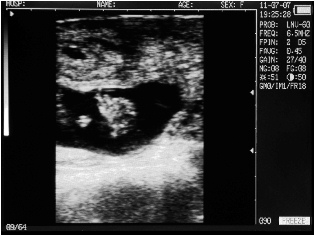

Filled bladder cow